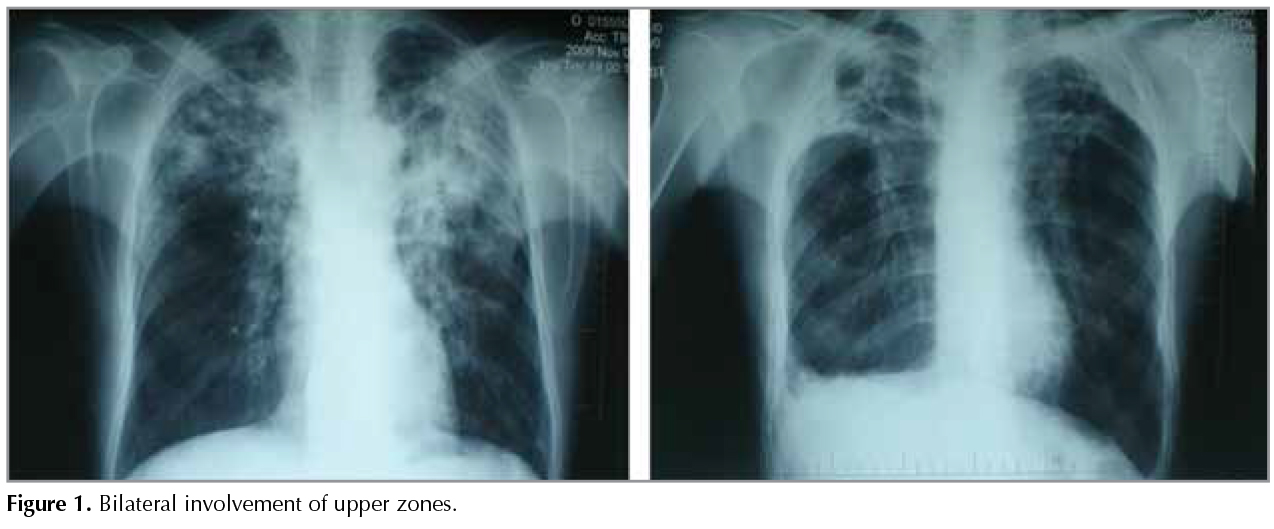

Plain chest radiography showed bilateral involvement of upper zones (Figure 1) in 5 patients, right middle zone in 1 patient, and cavity in 5 patients. Thoracic computed tomography (CT) revealed bronchiectasis in 5 patients, nodular opacities (micro-nodules with irregular borders) in 5, air cyst in 4 (as multiple air cysts, fig. 2), cavity in 3, peribronchial thickening in 3, sequelae in 4, ground-glass opacities in 3, pleural thickening in 5, minimal pleural effusion in 2, and enlargement of multiple mediastinal lymph nodes (diameter < 1 cm) in 4 (Table 3). Air cysts, bronchiectasis, and cavities were, generally, bilateral and in upper lobes whereas ground-glass opacities were seen in middle and lower lobes, and inferior and superior segments of the lingula.